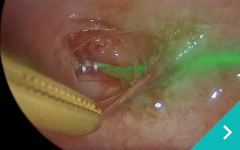

経皮的レーザー

椎間板減圧術(PLDD)

レーザー結石破砕